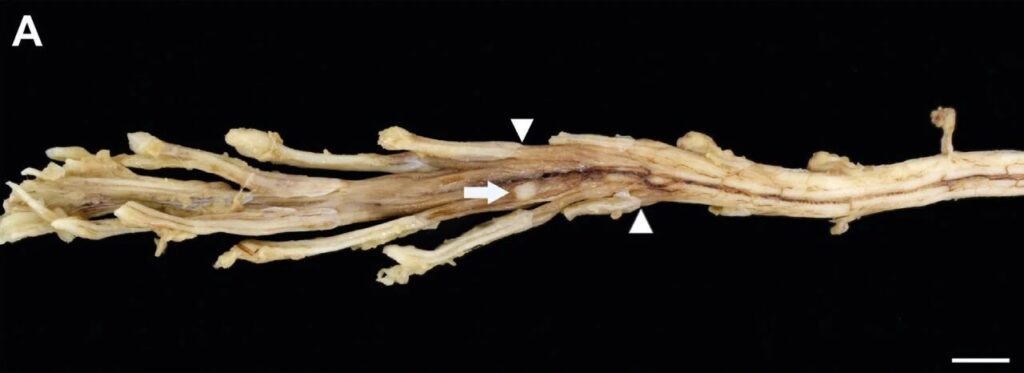

尸检显示脊神经根及神经节弥漫性增厚,并在右侧L6脊神经腹侧根处发现一处硬膜下米色肿块(0.4×0.3×0.2厘米)(下图)。组织学显示,颈髓第二、三节段(C2、C3)存在大淋巴细胞中度硬膜下浸润。在颈段C6、C7及腰段L2、L3、L6区域可见严重至完全性硬膜下、神经内及神经节内弥漫性至多灶性淋巴母细胞结节浸润。坐骨神经代表性切片显示轴突肿胀及髓鞘的沃勒氏变性。右侧臂丛神经可见类似病变,而左侧臂丛神经则呈现淋巴母细胞弥漫性神经内浸润。上述发现符合周围神经系统淋巴瘤特征,据此确诊为神经淋巴瘤。

↑(A)腰脊髓表现为脊神经根和神经节的弥漫性增厚。一个位于右侧L6脊神经腹根旁的丘状米色肿块(0.4 × 0.3 × 0.2 cm)(白箭头)。箭头指示从中枢到外周神经组织的过渡,组织突然增厚并呈米色变色,与组织病理学上可检测到的肿瘤细胞浸润相对应。